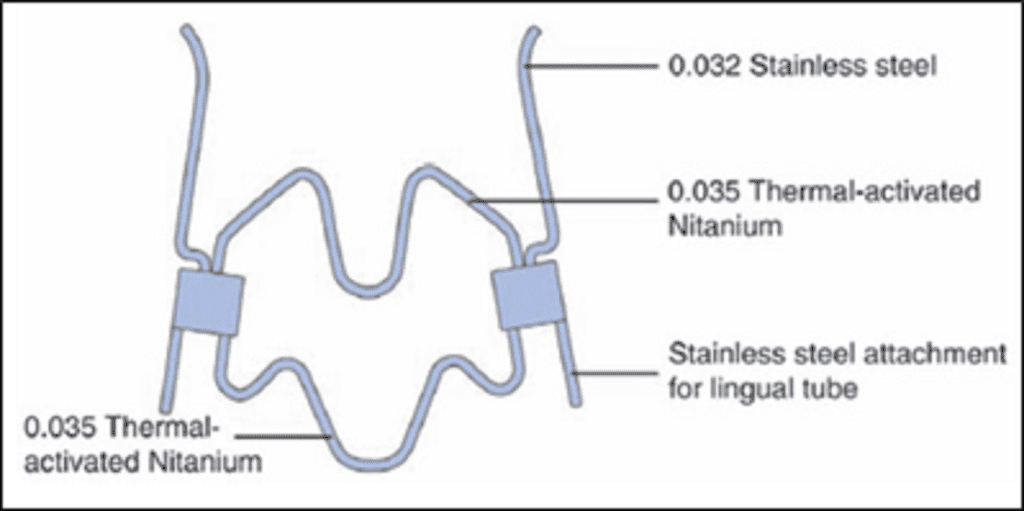

(F) Ni-Ti Expanders

Wendell V Arndt, in 1993, developed a tandem-loop NiTi, a temperature-activated palatal expander. This has the capability to produce continuous, light force on mid-palatal suture and uprights, rotates and distalizes maxillary first molars simultaneously.

Appliance Framework – This fixed appliance has stainless steel extensions that could be adjusted and inserted into standard horizontal lingual sheaths which are welded to the molar bands. An indent on the lingual attachment locks the expander to the molar band ensuring patient protection. For increased protection, an elastomer may also be placed.

The appliance has got a central component and a lateral component. The central component is made of thermally-activated NiTi alloy.the lateral arm, which is bracing the palatal aspect of the maxillary posterior teeth, is made of stainless steel.

Activation – At room temperature, the expander is too stiff to be compressed and inserted into the maxillary arch. The transition temperature of the NiTi alloy used in the expander is 94°F,which is close to intraoral temperature. For the appliance to be inserted into the mouth, it is chilled so that the central part softens and can be easily inserted.Once the appliance is fitted, the expander warms to the body temperature, becomes stiff and returns back to its original position. The expander delivers constant force as it deactivates.

The expander is available in various sizes from 26 to 44 mm in eight different intermolar widths generating 180–300 g of force. The 26–32 mm sizes have softer wires to produce low level force in children. Clinically, the correct size is estimated by measuring the amount of expansion needed and then by adding 3 mm as overcorrection.